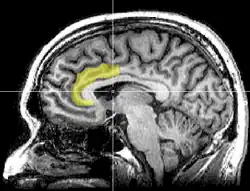

Envy and schadenfreude are related emotions. Takahashi, et al. (2009) looked at the areas of the brain that were active when feelings of envy and schadenfreude were evoked. Using functional magnetic resonance imaging (fMRI) researchers looked for activity in the dorsal anterior cingulate cortex (dACC) (seen in image 2.) when envy was felt, as the anterior cingulate cortex is the area that is activated when our positive self-concept is being conflicted with external information, social pain, or cognitive conflicts (Takahashi, et al., 2009). When investigating the emotion of schadenfreude they were looking for activation in the ventral striatum, which is the central node of the rewards processing area (Takahashi, et al., 2009). The reward would be the joy that is derived in schadenfreude. Takahashi, et al. (2009) found that both areas which were targeted in their respective trials activated when the respective emotion was emitted. They found that when people had higher levels of schadenfreude, greater activation was seen in the ventral striatum. This was also found to be the case when investigating envy. Greater levels of envy showed higher activation in the dACC (Takahashi, et al., 2009).